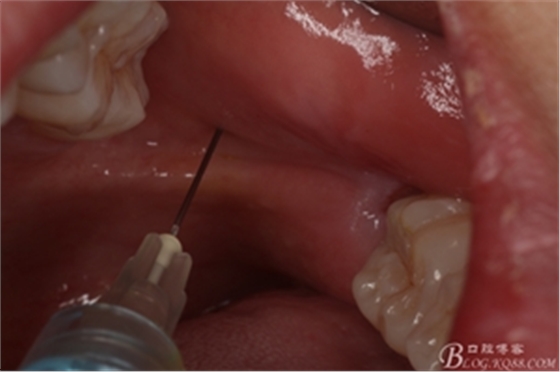

圖5.術(shù)前做好全面的檢查和風(fēng)險(xiǎn)評(píng)估,開始局部無痛麻醉。